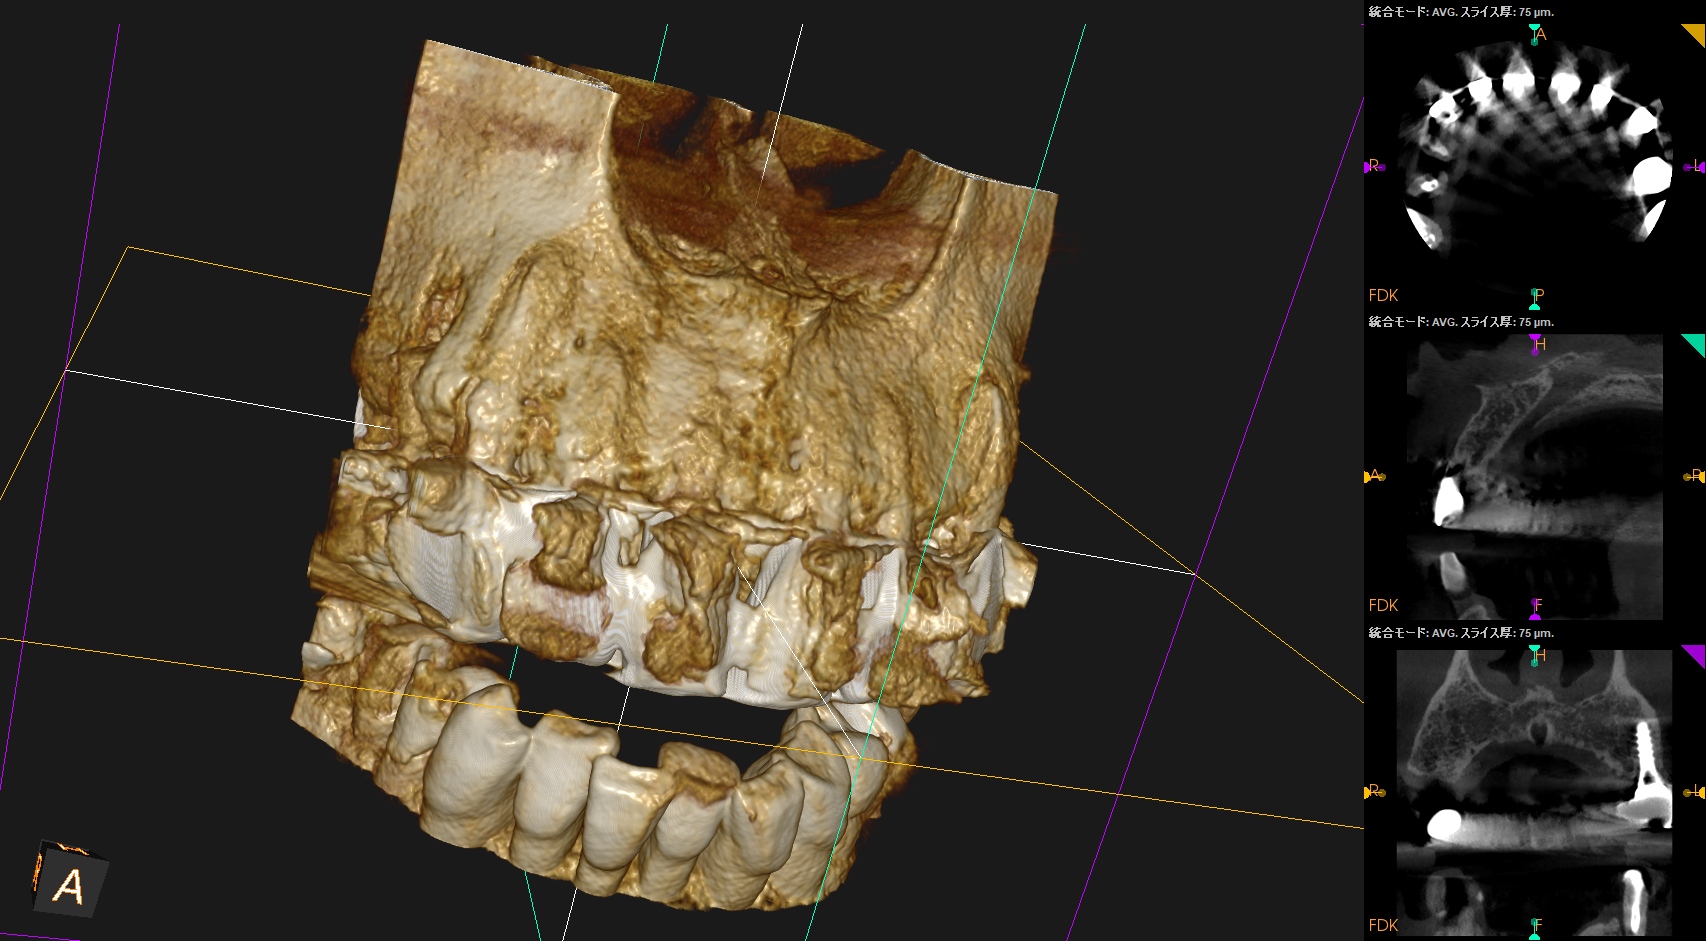

過去治療の経過観察。

外科処置から1年が経過した。

歯牙はどうなっただろうか?

#8

#9

#8,9(B)

初診時と比較した。

問題は大きく解決されている。

初診時のSinus tract, 臨床症状は消失した。

ということでこの2歯をこれ以上経過を見ていく必要はないだろう。

この日で終診とさせていただいた。